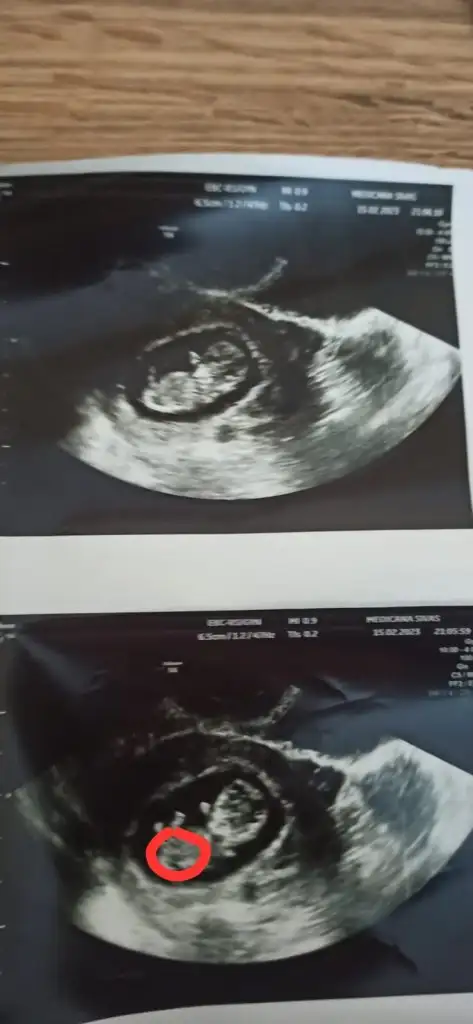

Bugün şu toxo sordum kızlar bir testi daha varmış oranına göre ilacı var dedi rabbime şükürler olsun biraz minnakız 7+0 olması lazım geç döllenme olmuş dedi bunada şükür hamdolsun resim koyarım pek gözükmüyoruz gerçi nefesimi tutarak kalbini duyduk Allah’ıma hamdolsun hepimiz sağlıkla kucağımıza alalım Rabbimin eli üzerimizde olsun